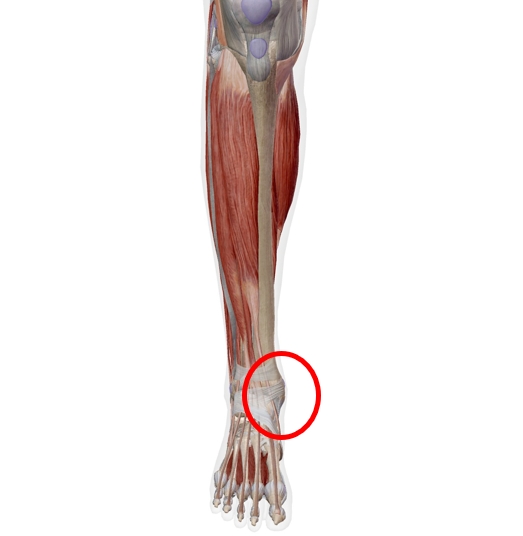

このあたりが痛むでしょうか?

原因①:後脛骨筋腱炎(扁平足が関係することも)

足首の内側の痛みでかなり多いのが、後脛骨筋腱(こうけいこつきんけん)の炎症です。

後脛骨筋は、足の内側に付いていて土踏まずを支える重要な筋肉です。

後脛骨筋は上の写真のように付着しています。よく見ると、足の裏の方まで続いていますね。

- 内くるぶしの後ろ〜下あたりが痛い(腱のあるあたり)